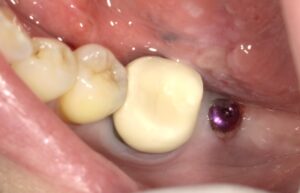

画像の様なイメージになります。針金を使いませんので

見た目がよくまた維持力も大きくとても良好な義歯となります。

取り外しの動画は下記になります。しっかりと装着されています。